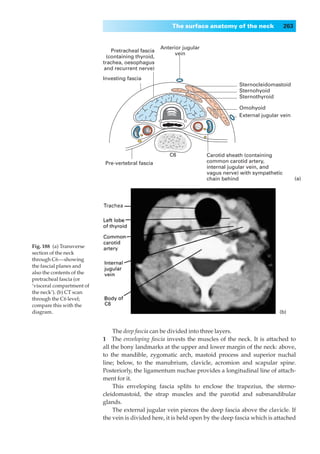

Pretracheal fascia   Anterior jugular

(containing thyroid,        vein

trachea, oesophagus

and recurrent nerve)

Investing fascia

Sternocleidomastoid

Sternohyoid

Sternothyroid

Omohyoid

External jugular vein

Fig. 16◊The cervical part                                C6             Carotid sheath (containing

of the trachea and its                                                  common carotid artery,

Pre-vertebral fascia

environs in transverse                                                  internal jugular vein, and

section (through the 6th                                                vagus nerve) with sympathetic

cervical vertebra).                                                     chain behind